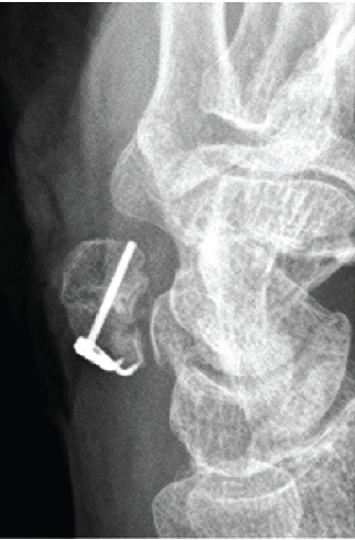

The procedure was performed under axillary block anesthesia with the patient in the supine position, and a pneumatic tourniquet was applied to the arm. A zigzag incision was made over the pisiform to expose the fracture site. The flexor carpi ulnaris (FCU) tendon was retracted radially to expose the fracture site. The site was debrided, and the proximal fragment was carefully mobilized using forceps. The distal impacted fragment was reduced under fluoroscopic guidance to restore joint alignment, and the proximally retracted fragment was repositioned anatomically to complete the reduction. For temporary stabilization, a 0.7-mm Kirschner wire was inserted distally into the proximal fragment. On inspection, the proximal fragment was deemed too small for definitive screw or wire fixation, consistent with the pre-operative assessment. Consequently, hook plate fixation was performed as planned. A 1.2-mm hook plate (APTUS Hand System; Medartis AG, Basel, Switzerland) was applied, with the hook engaging the proximal aspect of the pisiform. Interfragmentary compression was achieved by pulling the plate distally, followed by insertion of a cortical screw into the distal fragment to complete fixation (Fig. 3).

Figure 3: Intraoperative fluoroscopic image after hook plate fixation illustrates reduction and plate compression across the fracture, with the hook engaging the proximal aspect of the pisiform.

This construct provided stable fixation with interfragmentary compression, eliminating the need for direct fixation of the proximal fragment. The wound was closed in layers. Postoperatively, a volar forearm splint was applied with the wrist in a neutral position and maintained for 3 weeks.